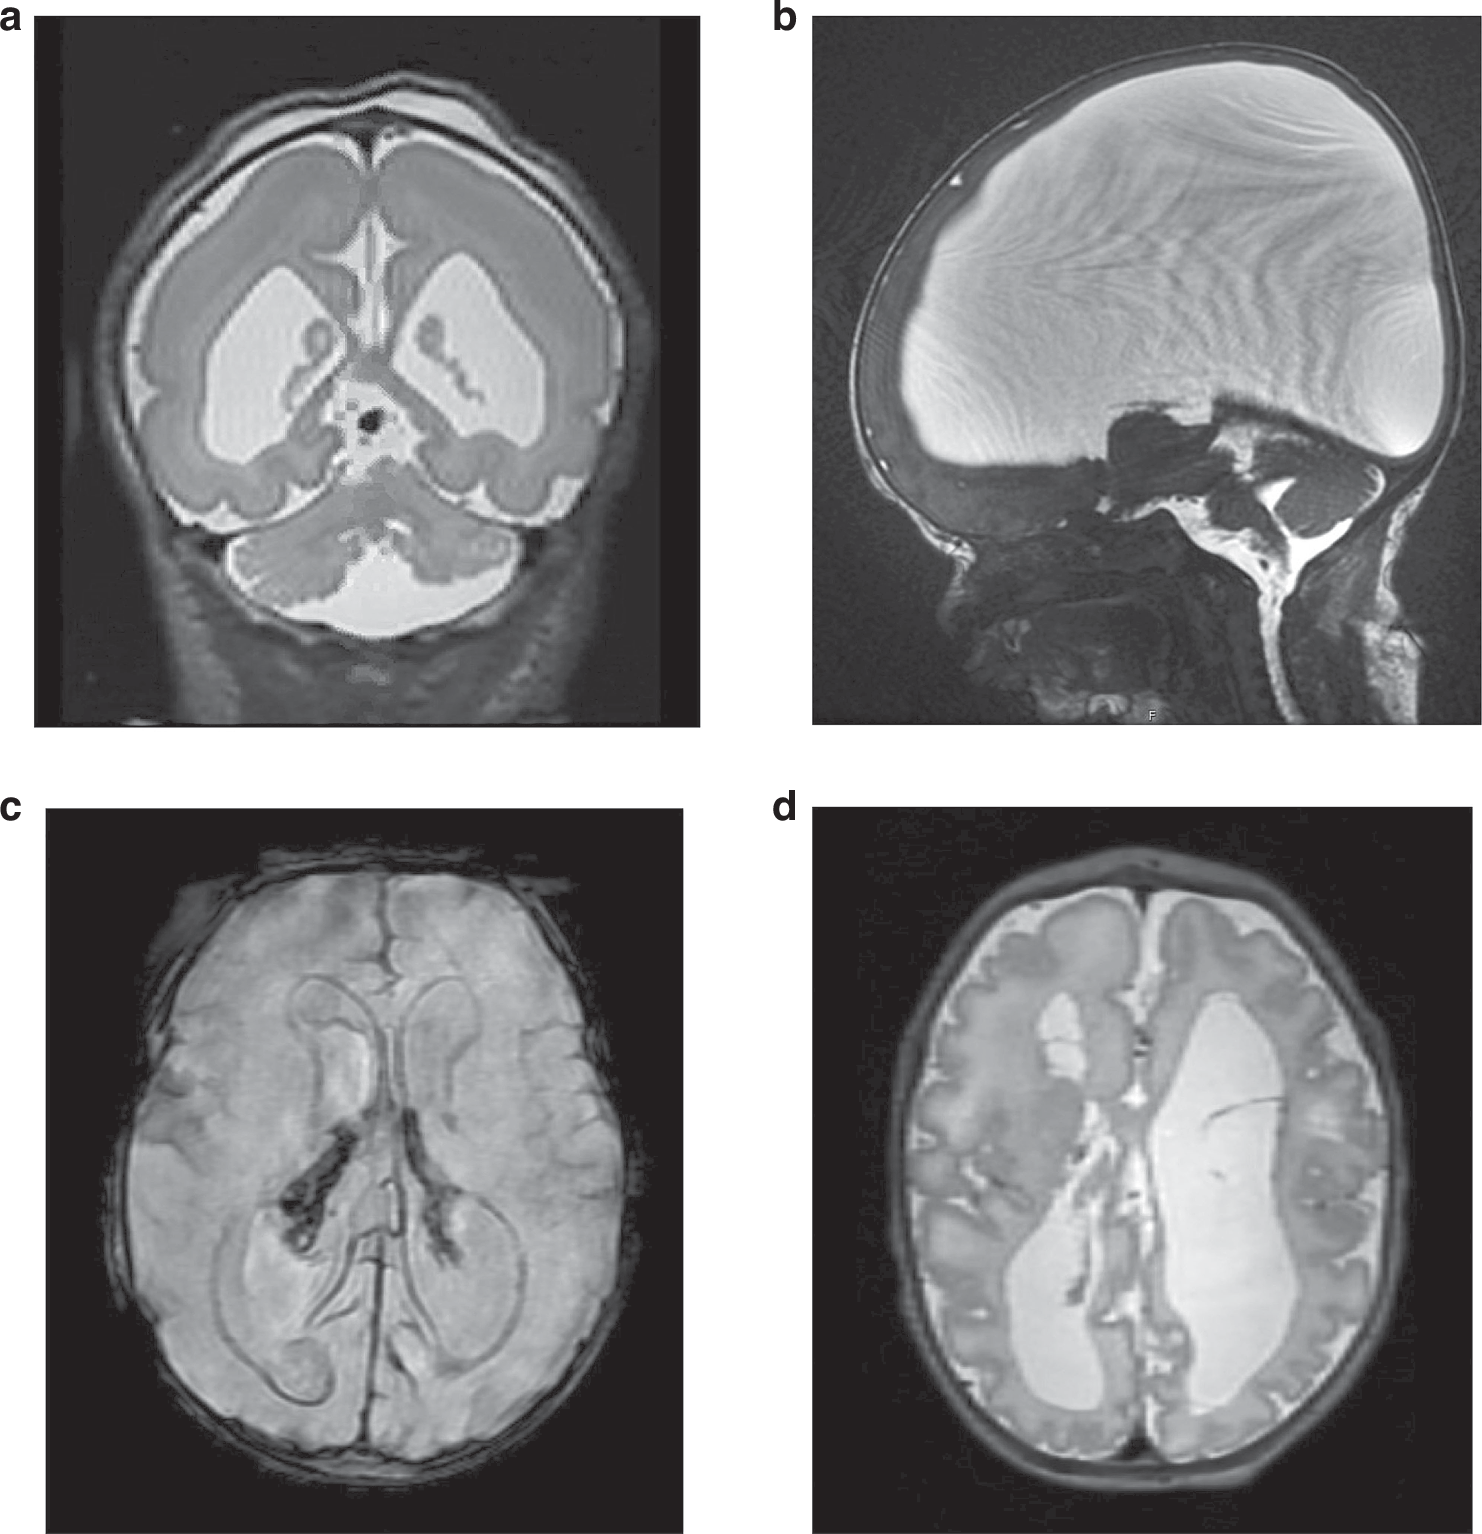

Fig. 2: Examples of neonatal MRI findings in selected genetic disorders with initial prenatal presentation.

From: Neonatal neurocritical care considerations for prenatally identified neurological disorders

a Coronal T2-weighted MRI in newborn with TUBA1A variant showing pachygyria-lissencephaly spectrum, ventriculomegaly, and cerebellar hypoplasia. Prenatal presentation in this case with ventriculomegaly on 38-week ultrasound for growth. b Sagittal T2-weighted MRI in newborn with L1CAM variant showing very severe ventriculomegaly due to aqueductal stenosis. Initial prenatal presentation with mild ventriculomegaly on anatomy ultrasound at 21 gestational weeks and progressive ventriculomegaly on ultrasound throughout pregnancy. c Susceptibility-weighted MRI in newborn with COL4A1 variant and prenatal diagnosis of intraventricular hemorrhage and right posterior periventricular hemorrhagic infarction with ventriculomegaly. Initial diagnosis on fetal brain MRI obtained at 37 gestational weeks for ventriculomegaly on follow up growth ultrasound at 35 gestational weeks. d Axial T2-weighted MRI in newborn with PDHA1-related pyruvate dehydrogenase complex deficiency showing agenesis of the corpus callosum, ventriculomegaly, cystic cavitation of the white matter, and diffusely abnormal sulcation. Prenatal presentation with similar findings on ultrasound and fetal brain MRI at 32 gestational weeks.